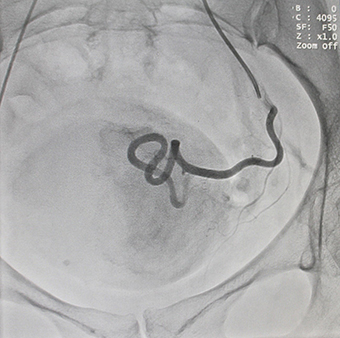

Эмболизация маточных артерий осуществляется рентген-хирургом в операционной,оснащенной ангиографической аппаратурой, под рентген-контролем. Доступом через бедренную или плечевую артерию при помощи специального катетера эмболизирующий препарат доставлен в артерии, питающие миому – последовательно справа и слева. Микроэмболы размером 500-700нм проникают в сосуды узла, блокируя их просвет, но в силу своих физических характеристик практически не попадают в сосуды, кровоснабжающие здоровые ткани. Питание тканей миомы прекращается, миома замещается соединительной тканью, уменьшается в размерах и как правило не требует дальнейшего лечения.

и после процедуры эмболизации![]() |

Таким образом, эмболизация маточных артерий это малоинвазивный и безопасный метод лечения: вероятность рецидива миомы минимальная, в большинстве случаев сохраняется способность к естественным родам. После эмболизации не требуется длительного пребывания в больнице. Обязательным является проведение контрольного УЗИ, которое подтвердит отсутствие кровотока в узле, после чего пациентка будет выписана и продолжит наблюдаться у врача акушера-гинеколога.